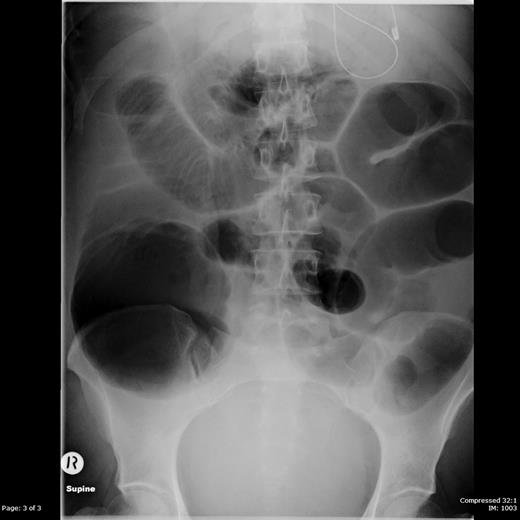

Increasing analgesic and antiemetic requirements prompted induction of labour at 38 weeks and 4 days gestation, with vaginal delivery of a baby boy. Despite clinical improvement initially, symptoms worsened again 24 h postpartum. She was no longer passing flatus and there were no audible bowel sounds. Repeat abdominal radiograph showed a large bowel obstruction with caecal dilatation up to 13 cm (Figures 1 and 2). The small bowel was also dilated, up to 5 cm.

Supine abdominal radiograph showing dilated loops of both large and small bowel.